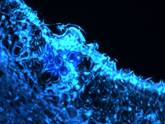

In the scattering images, the gold coated maghemite nanoparticles surrounded by melanoma can be seen as bright blue areas in UV light and as bright green areas in visible light. |

VISIBLE fluorescence microscopic image (Olimpus) of B16 melanoma after uptake of AuSPION (x 60). |

The intensity of the scattered light on gold nanoparticles uptaken in melanoma is 16 times more intense than the intensity of the light scattered on healthy tissue.

When endocytosis of nanoparticles occurs, the gold coated maghemite nanoparticles are surrounded with a melanoma dielectric coating.

In the scattering image, the gold coated maghemite nanoparticles surrounded by melanoma can be seen as bright blue areas in UV light.